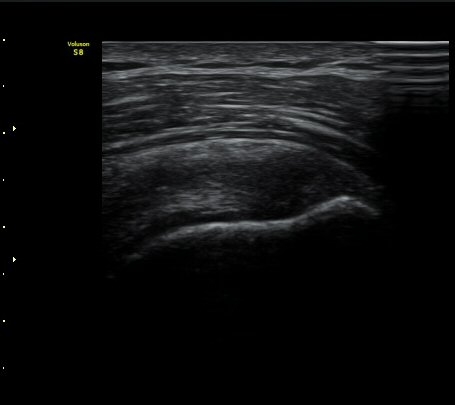

°ß°©ÇÏ±Ù°Ç »óºÎ Á¾´Ü¸é°Ë»ç»ó ¼Ò°áÀýÀÇÇÇÁú°ñÀÇ ºÒ±ÔÄ¢º¯È­¿Í °ß°©ÇÏ±Ù°Ç ¿¬°á¼º ¼Ò½ÇÀÌ

°üÂûµÊ(±×¸² 6, 7).